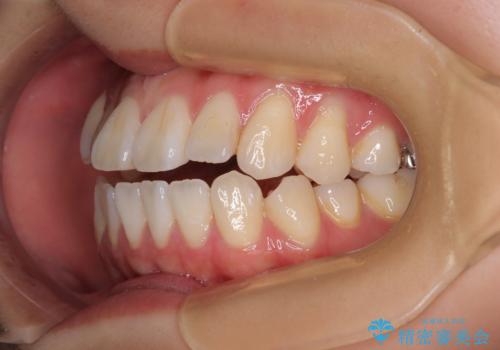

舌の突出癖が原因 インビザライン矯正による開咬改善

- 前歯の開咬を気にして来院された患者様です。

開咬の治療は、前歯を閉じるように動かすとともに、上下臼歯を圧下(骨内にめり込ませる)させることで進めて行きます。

インビザラインは臼歯の圧下を効果的に行えるため、インビザラインを用いて矯正治療を行うこととしました。